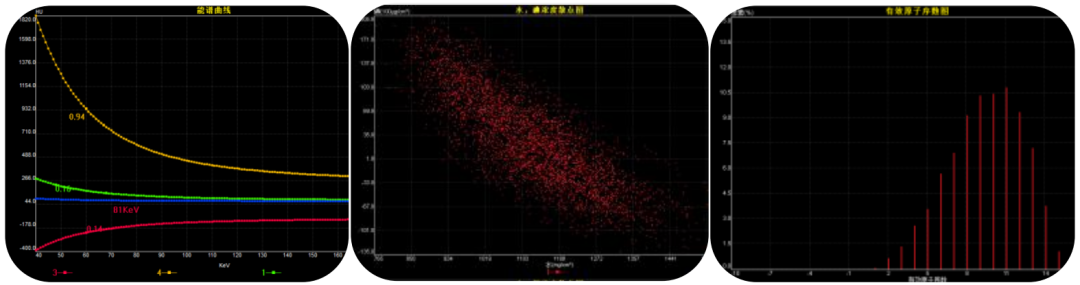

能谱基础分析技术

利用最佳 CNR 分析,可自动获得最佳单能量图像,更加清晰显示组织结构。对感兴趣区域的组织,可自由勾画 ROI 并进行智能测量分析,一键生成能谱曲线、散点图、直方图、有效原子序数图等多参数图像,结合能谱曲线斜率测量分析,实现病变的突出显示、肿瘤的同源性分析、病变成分高级分析等临床应用,同时为临床科研提供参考数据。

Mono 单能分析

多层面同步显示高、低能量图、虚拟能量图,快速实现151个能级分析,可任意生成40KV—190KeV区间的虚拟能量图像,医生可以根据每个患者的特性去调节KEV,得到理想的图像效果,比如金属伪影的去除、病变的突出显示、图像效果的优化等,从而更直观准确的去诊断病变。